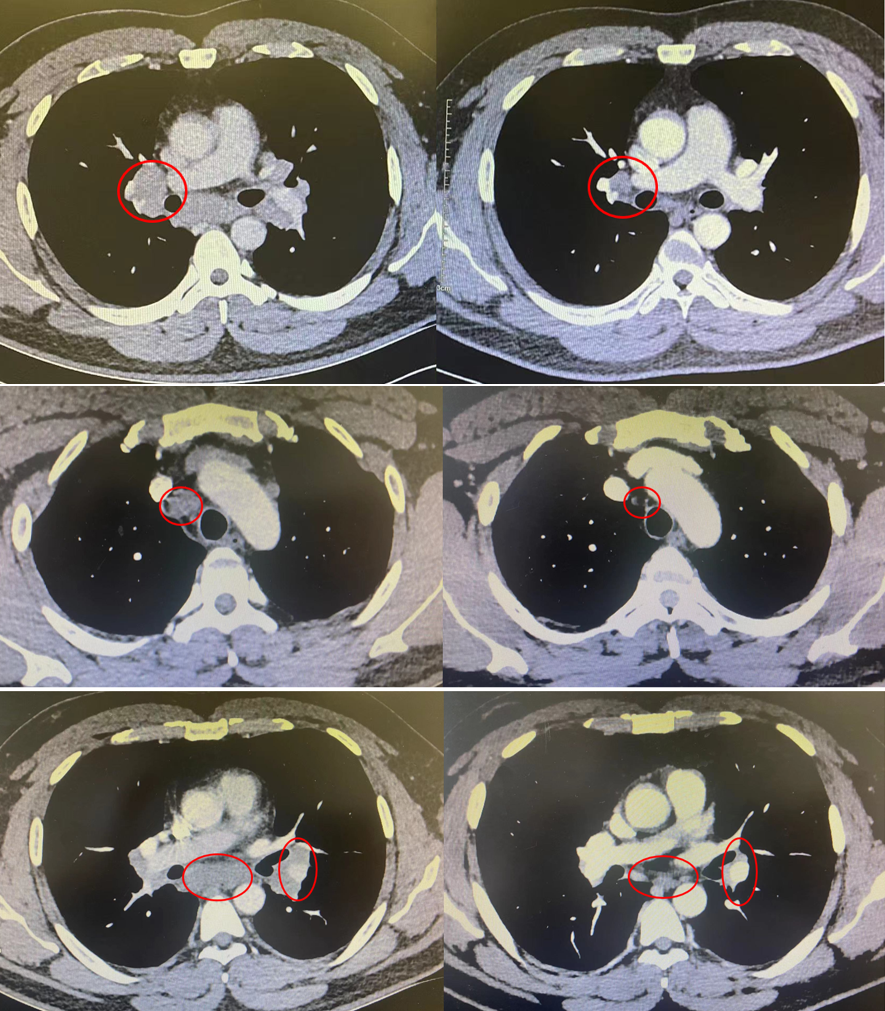

治疗刚陷「两难抉择」又起脑膜占位风波?何处觅真凶?

淋巴结较前缩小(图4),头颅增强核磁共振可见脑膜占位较前相仿(图5)